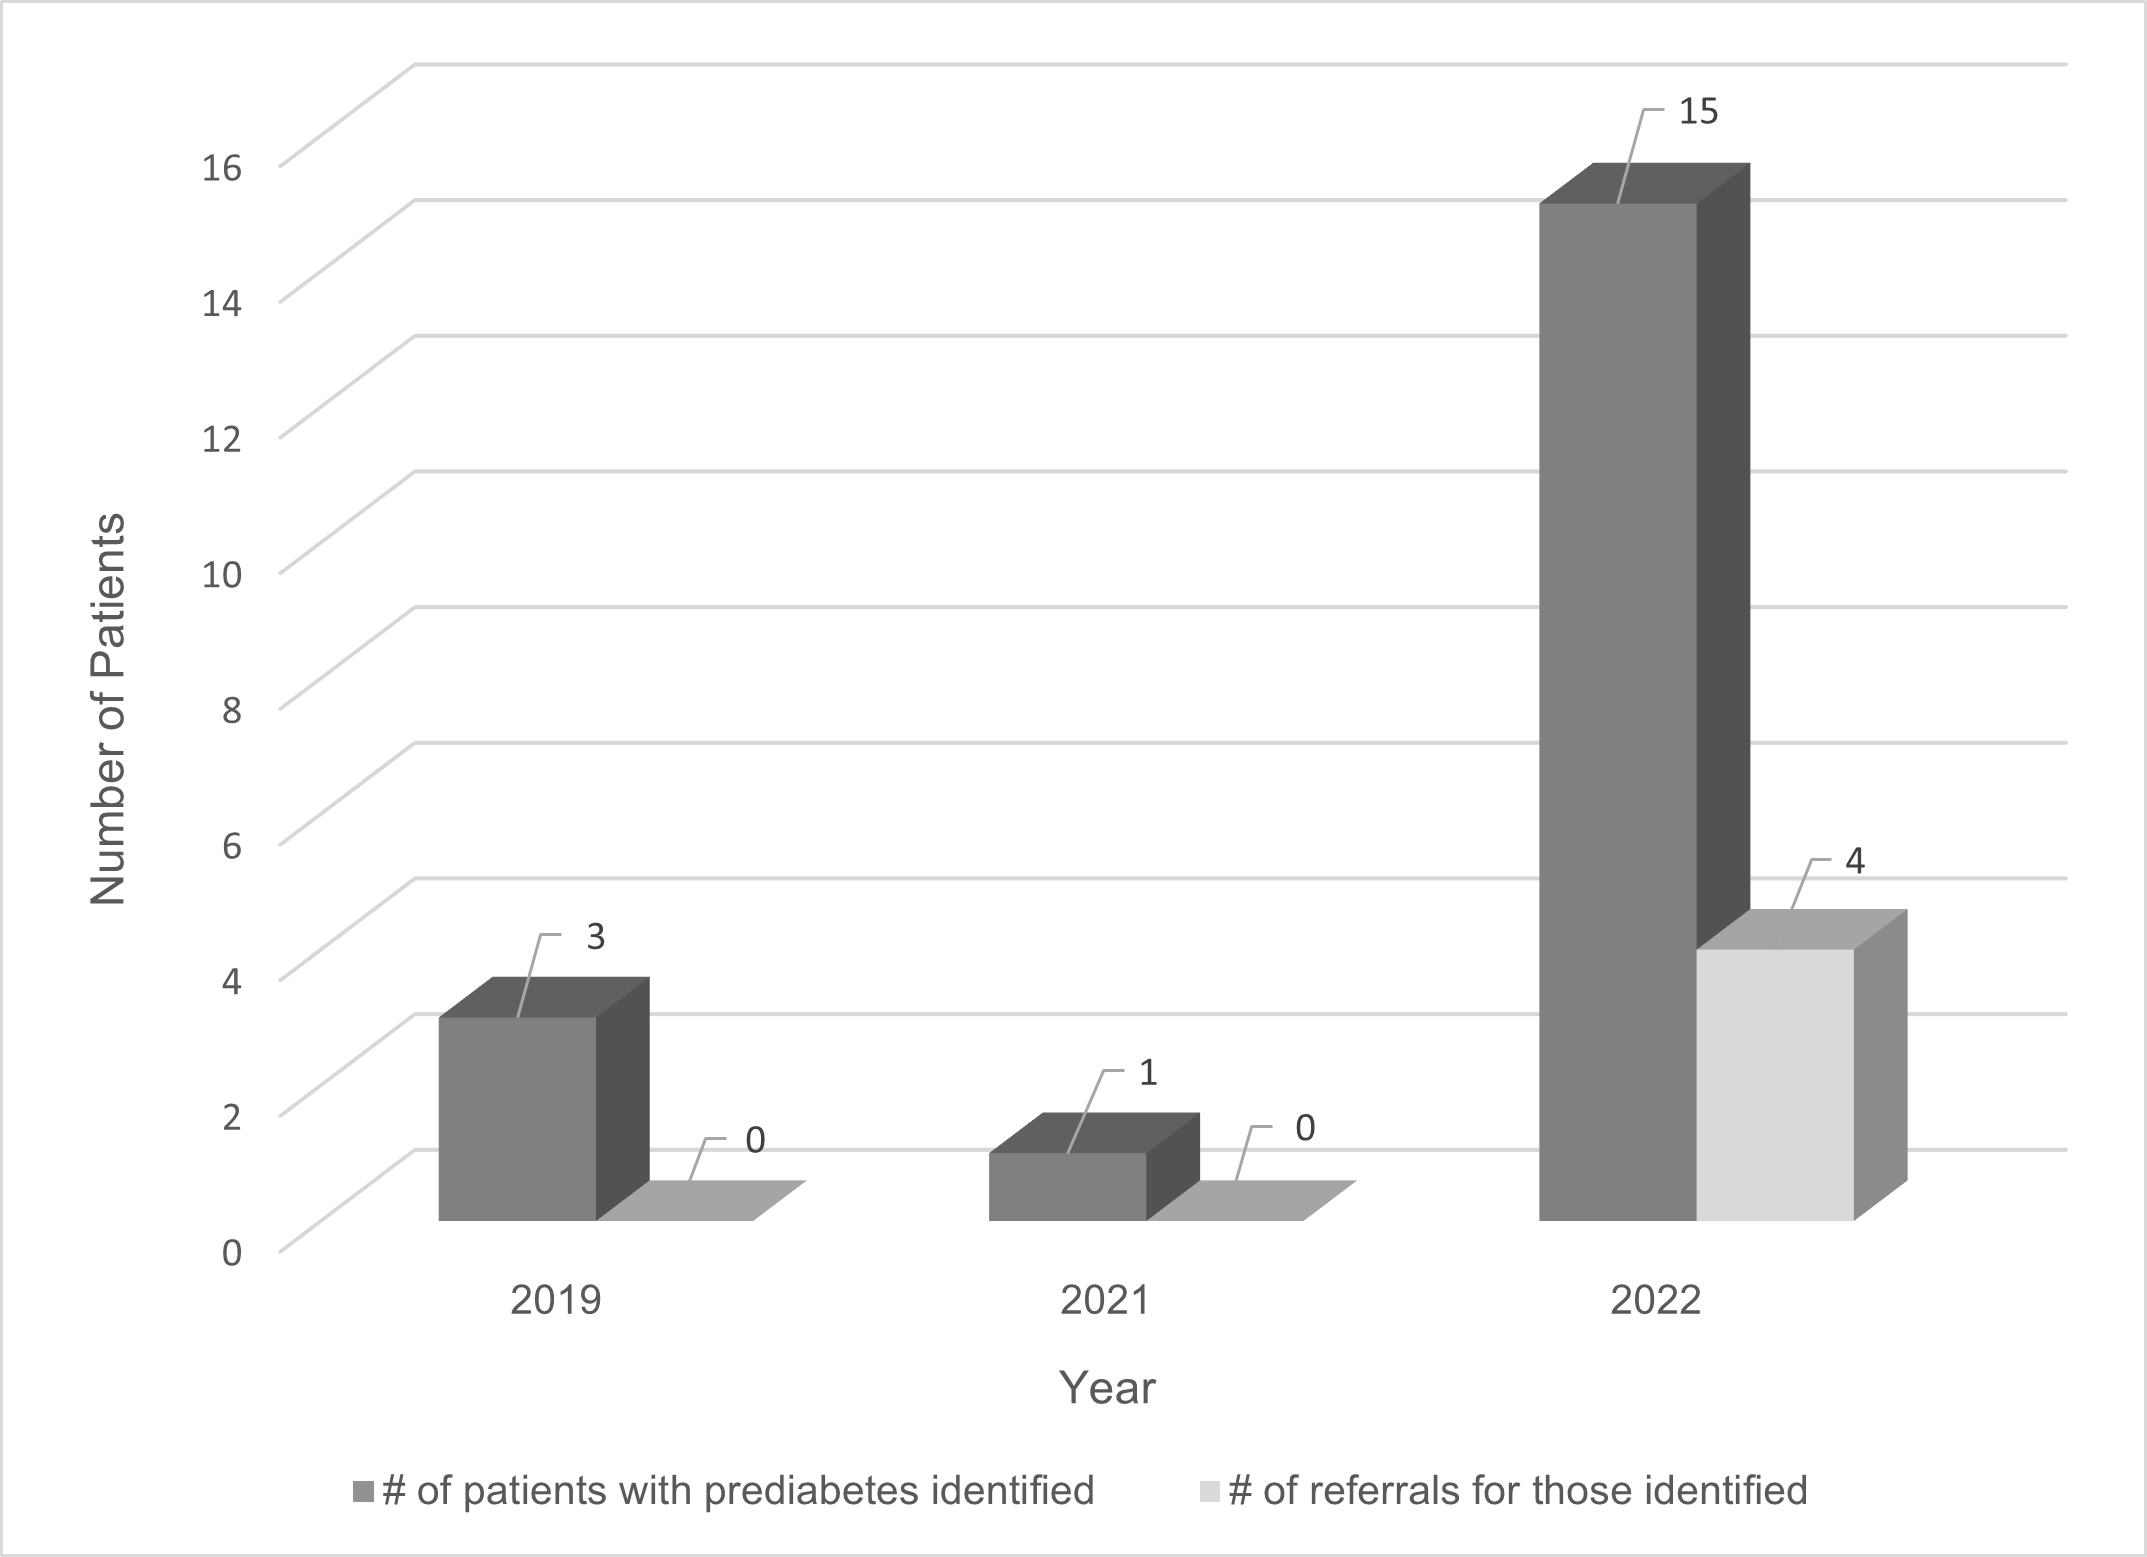

Quality Improvement Projects | Dec 01, 2025

Implementing a Prediabetes Screening Algorithm to Improve Identification and Referrals in Primary Care

Almost half (49%) of the United States population has prediabetes or type 2 diabetes. Type 2 diabetes is associated with...Read More